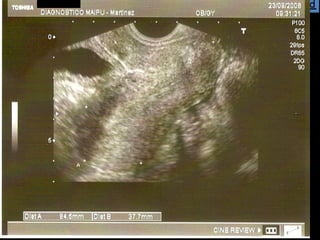

La ecografía ginecológica transrrectal es una ecografía endocavitaria que usa la vía transrrectal en lugar de la transvaginal. Se indica principalmente para pacientes vírgenes con ecografías ginecológicas no concluyentes, pacientes con vaginismo severo o hipotrofia marcada del introito y vagina. La técnica es similar a la ecografía transvaginal pero sin el tope vaginal, y permite imágenes casi idénticas.